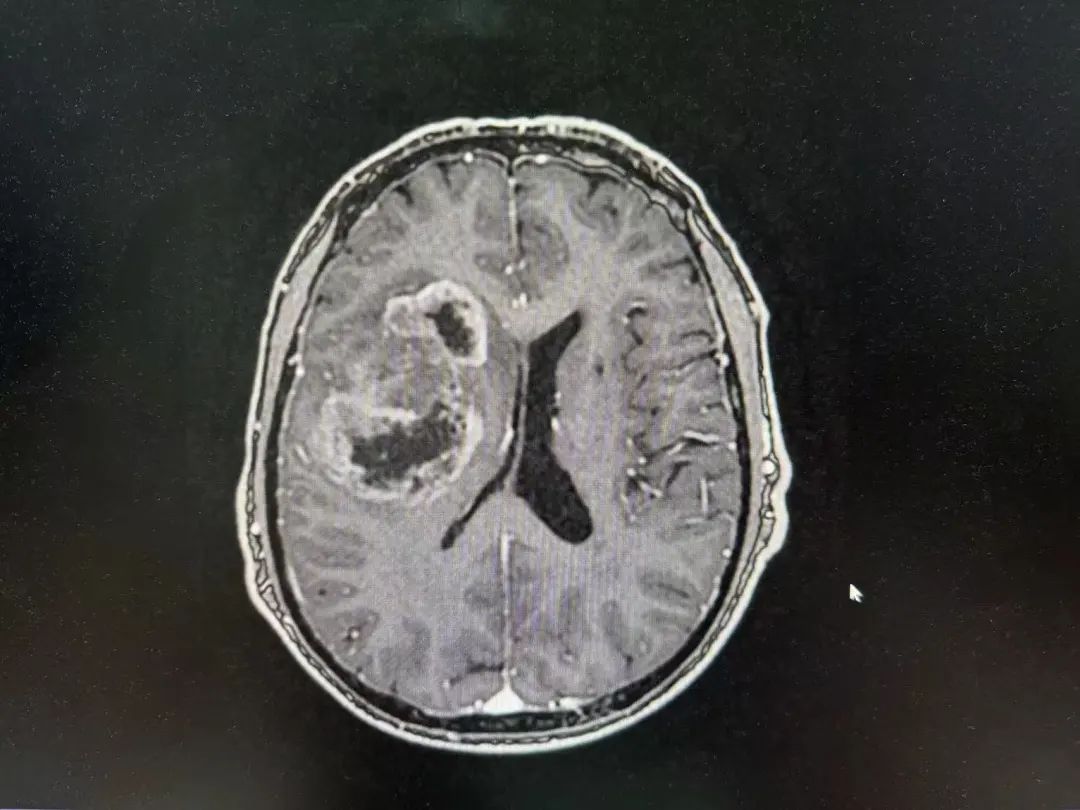

男性 | 67歲

主訴:左側(cè)口角流涎10天,左側(cè)肢體無力7天。

MR:右側(cè)大腦半球腫瘤性病變,考慮高級別膠質(zhì)瘤(大者大小約3.8cmx4.6cmx3.4cm)。